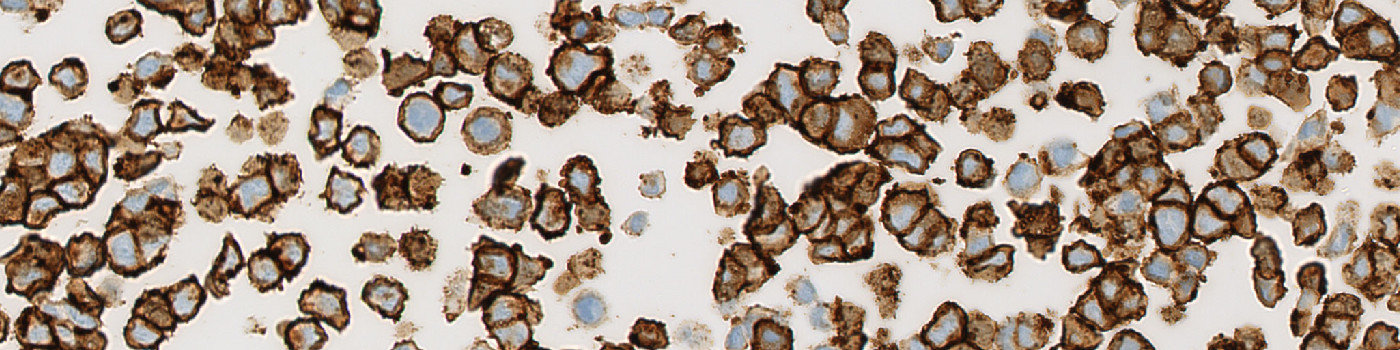

Raw image of cell line cores with different HEr2 expression.

The availability of genetically defined reference materials, offers an industry standard for development and quality control of IHC assays, directly, thereby improving the accuracy and reproducibility. Using engineered cell lines as quality control material to assess the performance of IHC assays eliminates the variability associated with patient-derived reference standards.

This APP can be used for quality control of HER2 negative (i.e. 0), 1+, 2+ and 3+ cell line material to ensure that each cell line block complies with the expected HER2 expression before the material is used as reference standard for IHC assays. The APP quantifies the HER2 expression in each cell line core and relates this expression to a known reference value for each cell line expression level.

First, a pre-processing step identifies the stained membrane pixels that contribute to linear structures in the image. Then, segmentation rules are employed identifying the membrane segments in the image. The segmentation is based on the intensity of brown in the pixels and the correct dimensions of linearity. After identifying pixels that constitute to brown linear structures and make up part of a membrane segment, post-processing steps are employed. The post-processing steps are used to skeletonize the membrane, removing small membrane fragments and merging membrane fragments which are not perfectly connected. From the membrane fragments remaining after post-processing, the connectivity can be calculated. Finally, the connectivity is translated into a classical HER2 score of 0, 1+, 2+ or 3+ based on known connectivity reference values for HER2 cell line cores expressing a score of either 0, 1+, 2+ or 3+.